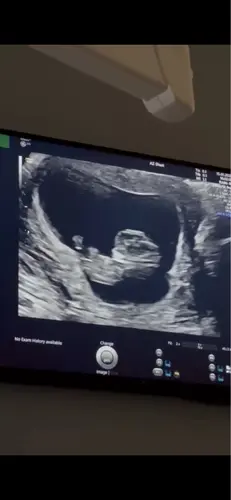

11w 3 was heel actief

De mijne dacht een koprol te doen 🤣